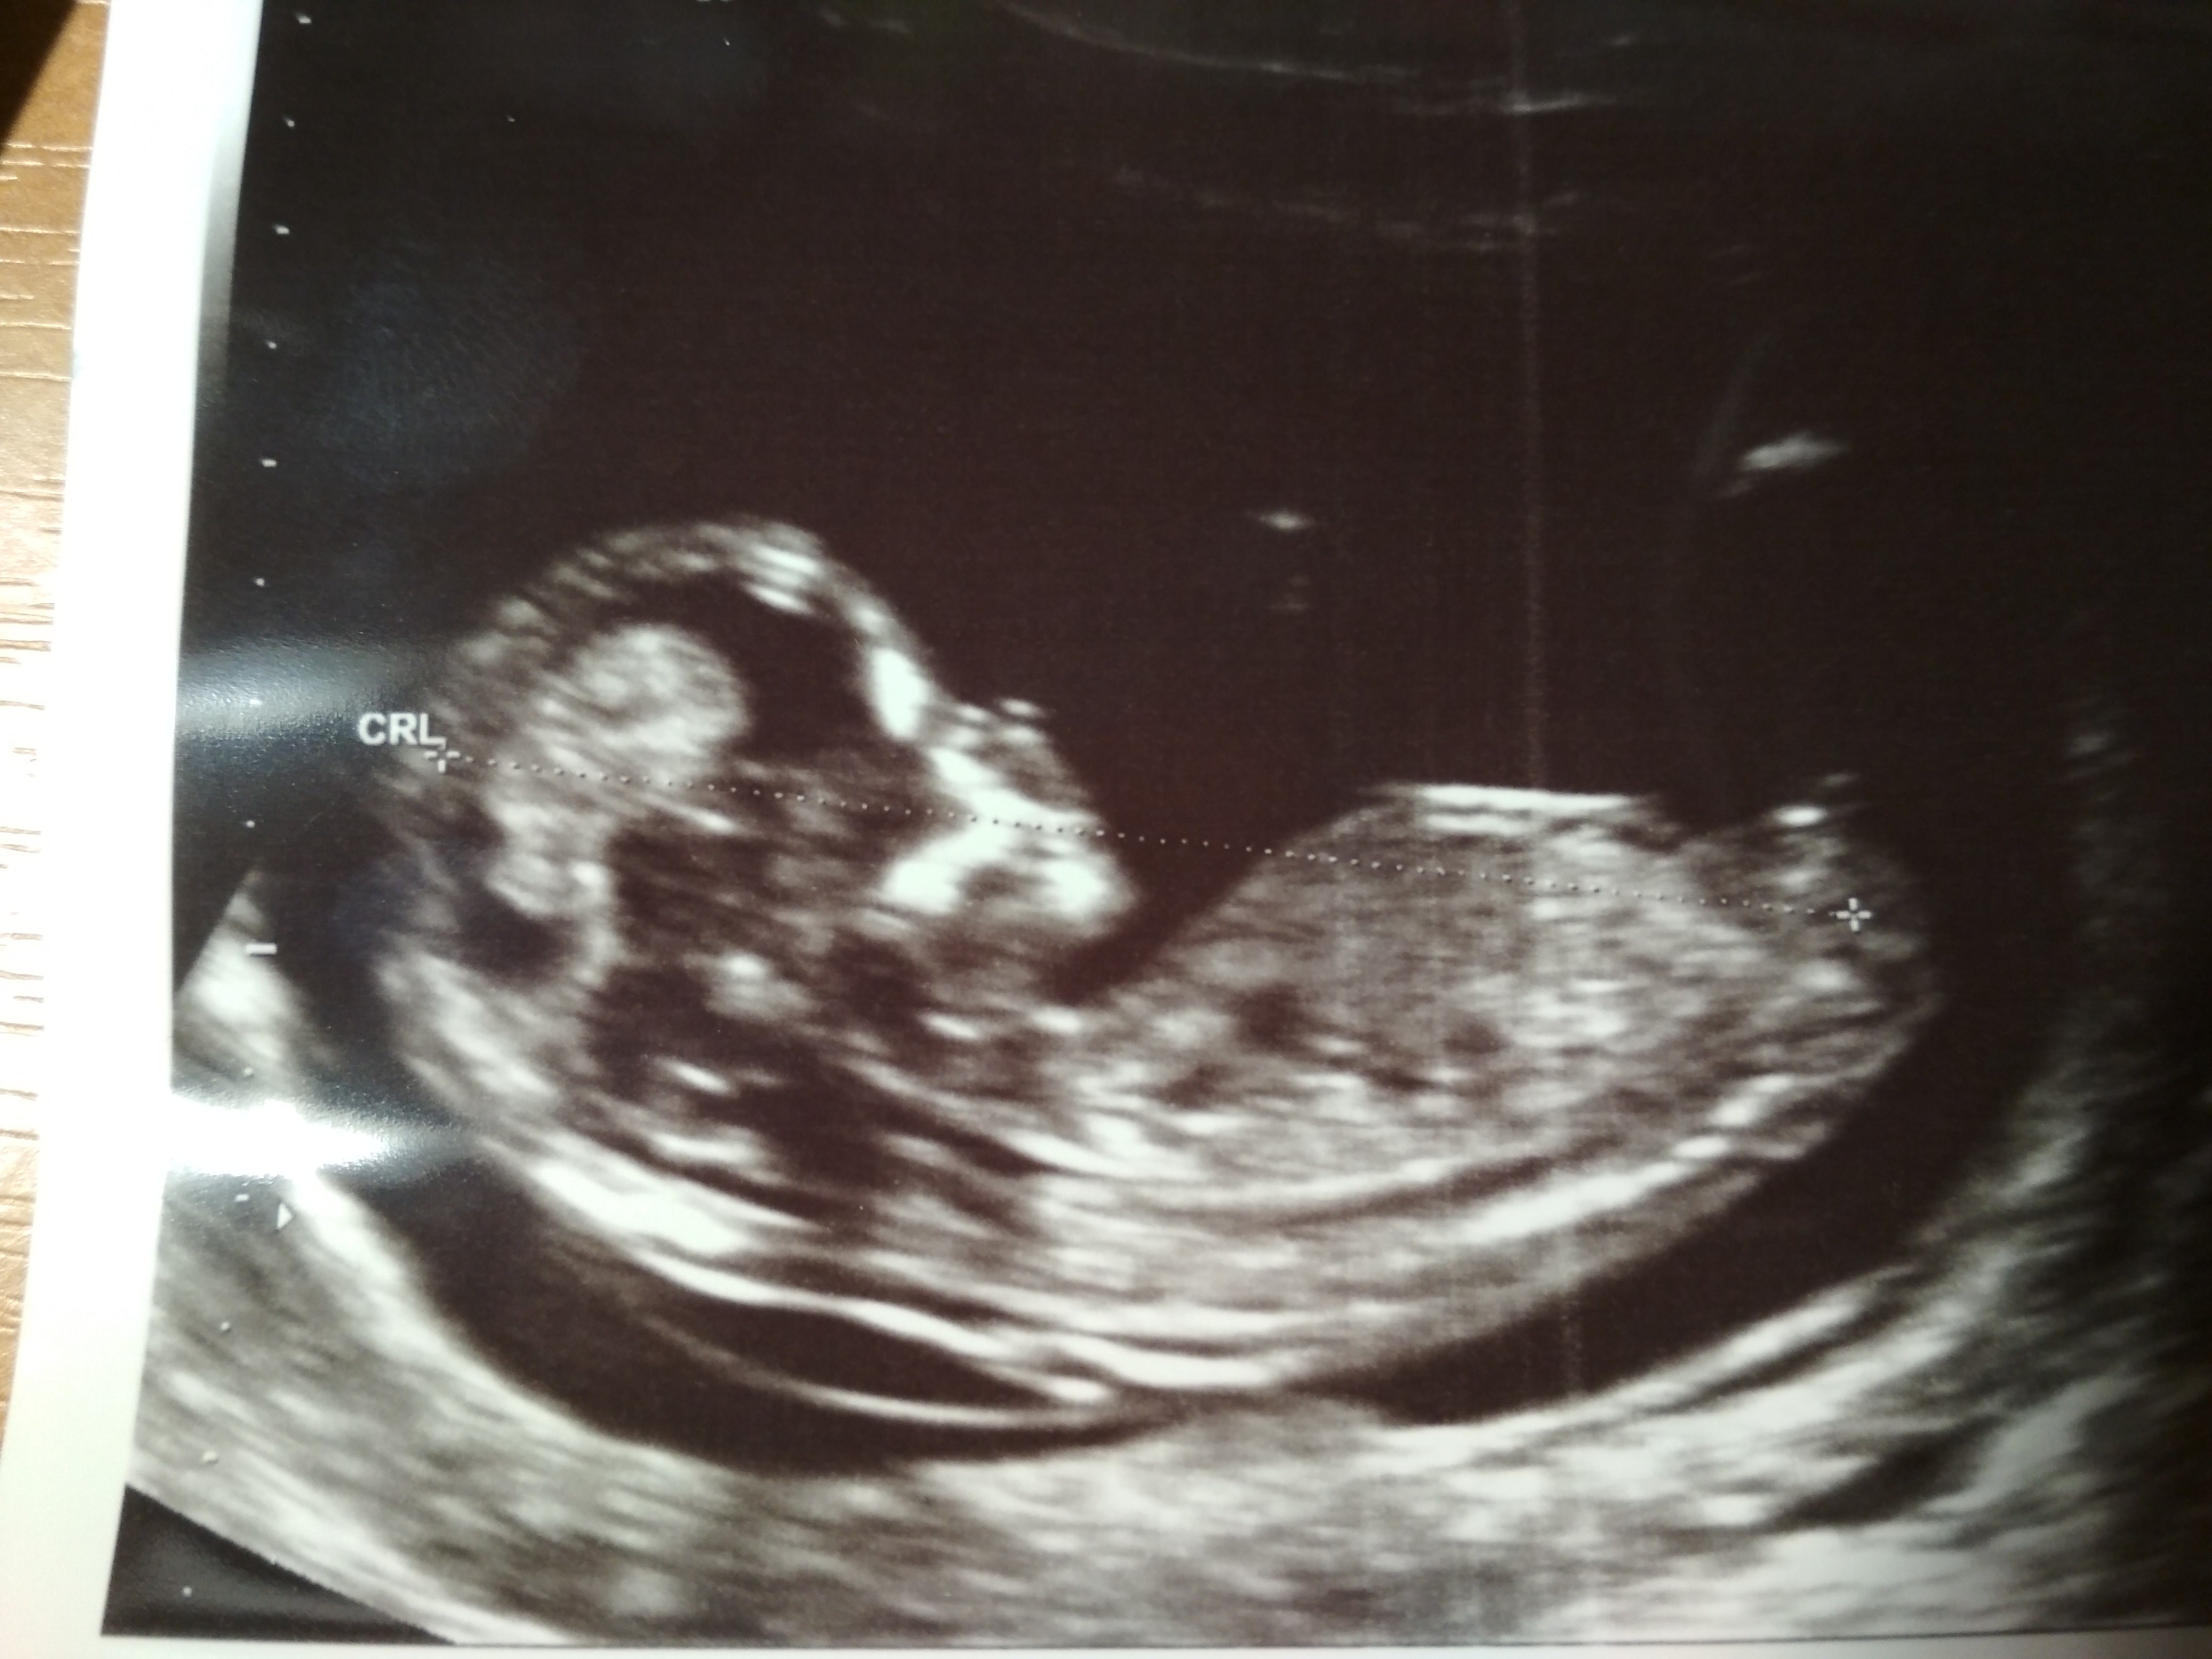

12tc. USG, chłopak czy dziewczyna?

Cześć dziewczyny, mam zdjęcia USG z 12tc+3d, podobno można stwierdzić płeć po wyrostku. Co myślicie? dziękuję za każdą odpowiedź

najlepiej mieć filmik z usg, wtedy można sobie obejrzeć dziecko w różnych układach